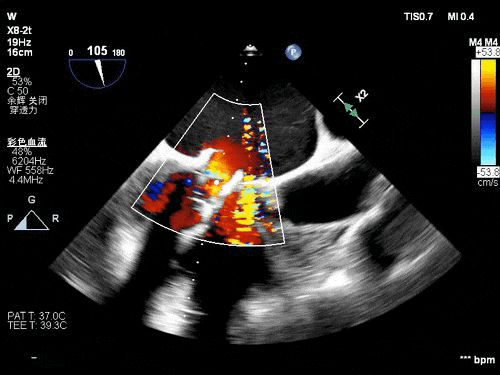

术前TEE影像

术后TEE图像

瓣膜释放后超声观察无瓣周漏,峰值流速0.76m/s,峰值压差5mmHg,平均压差2mmHg,流出道峰值流速1.28m/s,峰值压差7mmHg。